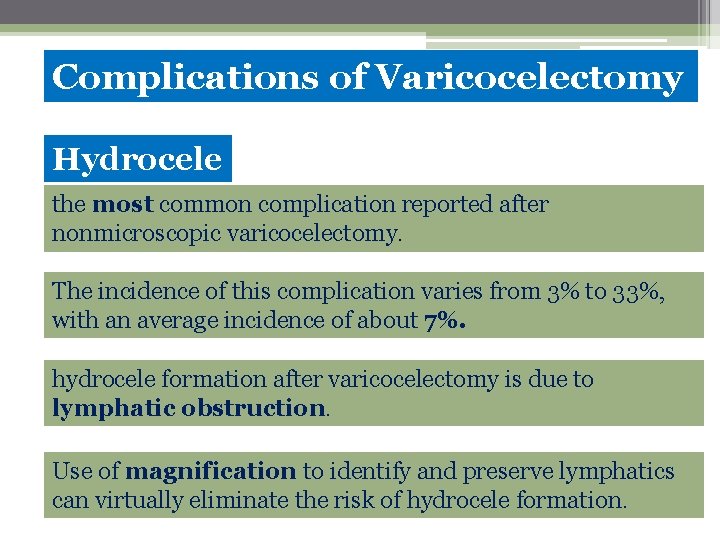

Complications of Varicocelectomy Hydrocele the most common complication reported after nonmicroscopic varicocelectomy. The incidence of this complication varies from 3% to 33%, with an average incidence of about 7%. hydrocele formation after varicocelectomy is due to lymphatic obstruction. Use of magnification to identify and preserve lymphatics can virtually eliminate the risk of hydrocele formation.